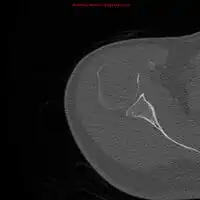

Skeletal surveys are used to ensure there are no other primary tumors within the axial skeleton. MRI can be used to assess tumor status and may be advantageous in detecting primary tumors that are not detected by plain film radiography. PET-CT may also be beneficial in detecting extramedullary tumours in individuals diagnosed with SPB. CT imaging may be better than plain film radiography for assessing bone damage.[6][7]

Imaging